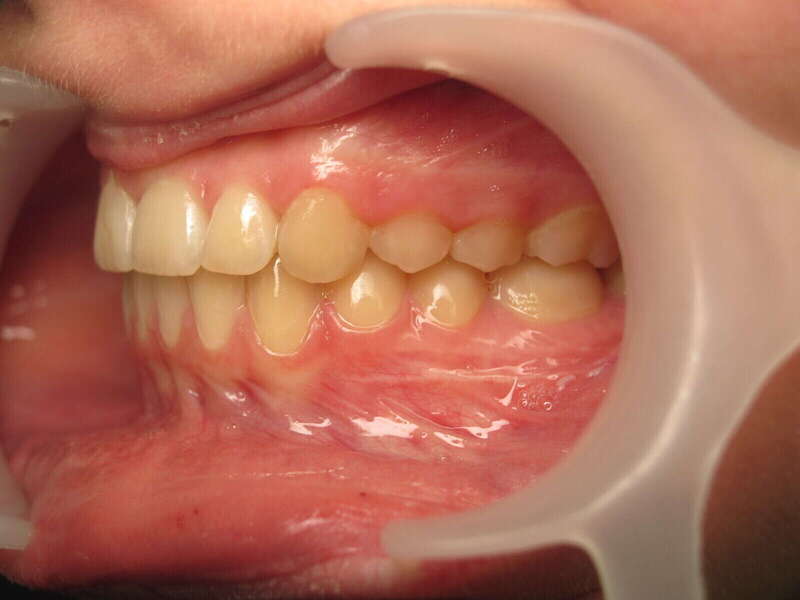

Ce cas d’interception chez un enfant de 8 ans démontre l'efficacité des aligneurs pour corriger des troubles fonctionnels précoces. Le diagnostic présentait des inversions d'articulé provoquant une déviation de la mandibule vers la gauche et un décalage des milieux.

Grâce à une coopération exemplaire et un traitement totalement indolore, l'expansion de l'arcade a permis de recentrer la mâchoire. Cette intervention a littéralement remis la croissance sur les rails, neutralisant le risque d'asymétrie faciale squelettique.

• Correction fonctionnelle : Recentrage immédiat de la mandibule et des milieux inter-incisifs.

• Prévention : Création d'un environnement favorable pour les dents définitives à venir.